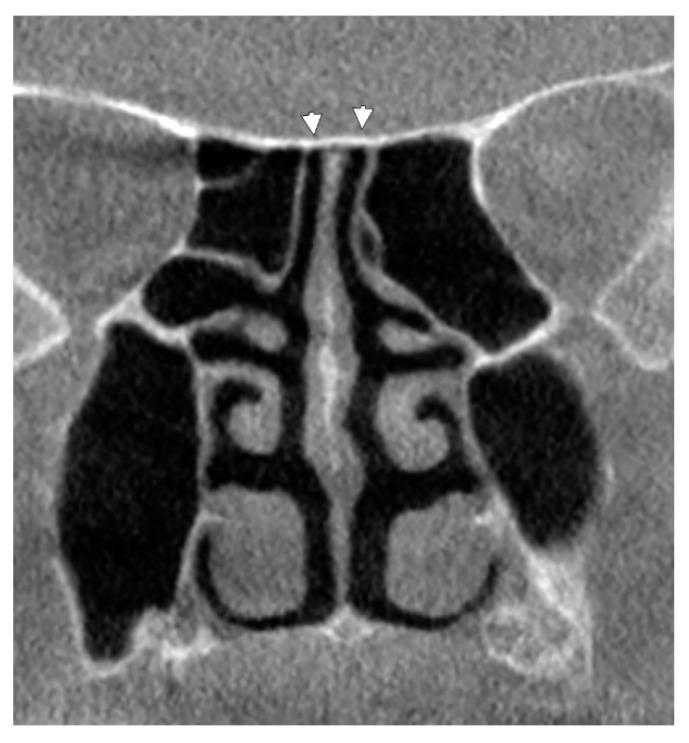

For good surgical performance, sound knowledge of anatomy is required. Although the ethmoid air cells and sphenoid sinuses are subject to a high degree of variation, their possible extensions above the nasal fossa at the posterior end of the cribriform plate of the ethmoid bone (CPEB) were seemingly overlooked. We retrospectively studied 162 case files from 55 male and 107 female cases, with ages varying from 42 to 80, which were scanned using Cone Beam Computed Tomography. In 56.17% of cases, an unpneumatized CPEB (type I) was found. Nasal roof recesses of ethmoidal origin (type II) were found at the posterior end of the CPEB in 20.37% of cases. Different types of sphenoidal pneumatizations of the posterior end of the CPEB (type III) were found in 22.83% of the cases. Onodi cells projected nasal roof recesses (type IV) in only 10 cases. In all types, nasal roof recesses were found either above the CPEB or within/underneath it. Moreover, such nasal roof recesses were found to be either unilateral, extended contralaterally, or bilateral. As such recesses of the posterior CPEB, previously overlooked, belong to the posterior rhinobase, they should be carefully documented preoperatively to avoid unwanted surgical damage to the olfactory bulb or CSF fistula.

为了获得良好的手术效果,需要对解剖学有扎实的了解。尽管筛骨气房和蝶窦的结构具有高度的可变性,但人们似乎忽略了它们在筛骨筛板后端(CPEB)鼻腔上方可能的延伸。我们回顾性地研究了 162 例 55 名男性和 107 名女性的病例文件,这些患者的年龄从 42 岁到 80 岁不等,他们均使用锥形束 CT 进行了扫描。在 56.17%的病例中,我们发现了未气化的 CPEB(I 型)。在 20.37%的病例中,我们在 CPEB 的后端发现了筛骨起源的鼻顶隐窝(II 型)。在 22.83%的病例中,我们发现了不同类型的 CPEB 后端蝶窦气化(III 型)。仅在 10 例中发现了 Onodi 细胞突出的鼻顶隐窝(IV 型)。在所有类型中,鼻顶隐窝要么位于 CPEB 上方,要么位于 CPEB 内部/下方。此外,这些鼻顶隐窝可能是单侧的、向对侧延伸的或双侧的。由于之前被忽视的 CPEB 后端的这些隐窝属于后鼻基底,因此应该在术前仔细记录,以避免对嗅球或 CSF 瘘管造成不必要的手术损伤。